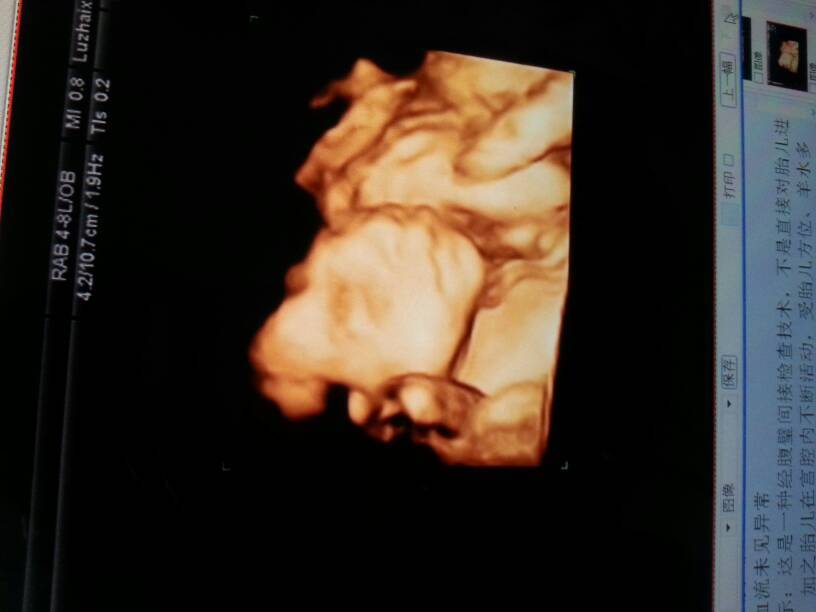

看看我家宝贝像男孩女孩 看看我家宝贝像男孩女孩 点击展开 紫萱宝贝418125 2015-05-07 10:14 为您推荐: 其他回答 看不出来d 小子ゝ想怎樣ˊ_>ˋ 2015-05-07 16:17 看着像男孩,好可爱 家有俩宝贝真幸福 2015-05-07 11:17 看不出来, 一抹尘埃、一季繁华落尽_Rqfu 2015-05-07 11:12 看不出来。 智、烨妈咪 2015-05-07 10:40 像男!!!!! 唐糖~唐果 2015-05-07 10:23 加载更多 相关问题 看看我家宝宝男孩女孩 大家看看我八个月的肚子男孩女孩 可人家算是女孩 一点妊娠纹没长 皮肤还特别白 看看我家宝贝儿这是长的什么?